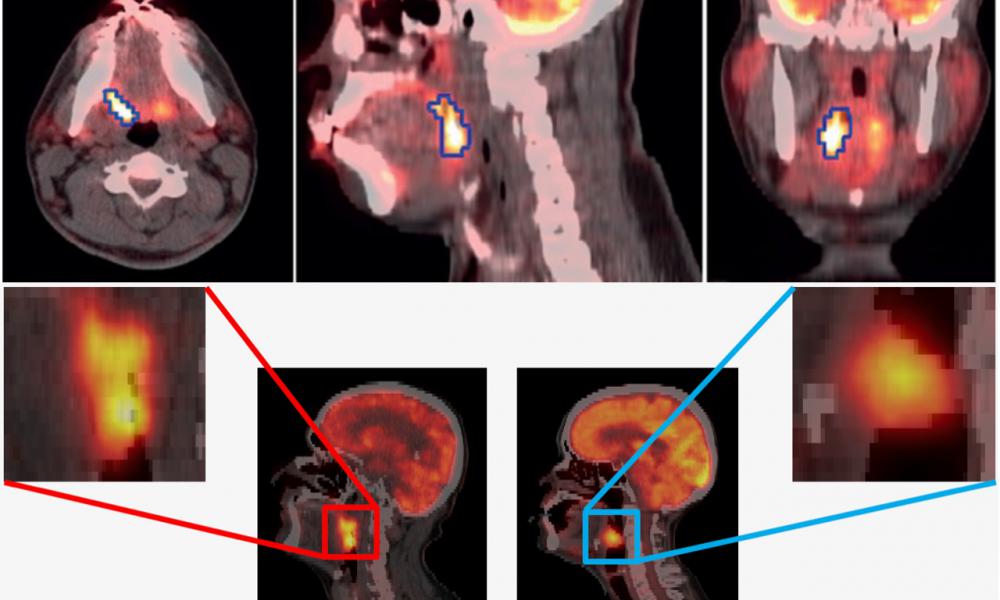

- Quantitative PET/CT imaging methods for enhanced diagnosis, prognosis and treatment response assessment of cancer patients

- AI and Radiomics methods as applied to PET and SPECT imaging for improved assessment of cancer, including physician-in-the-loop AI solution development